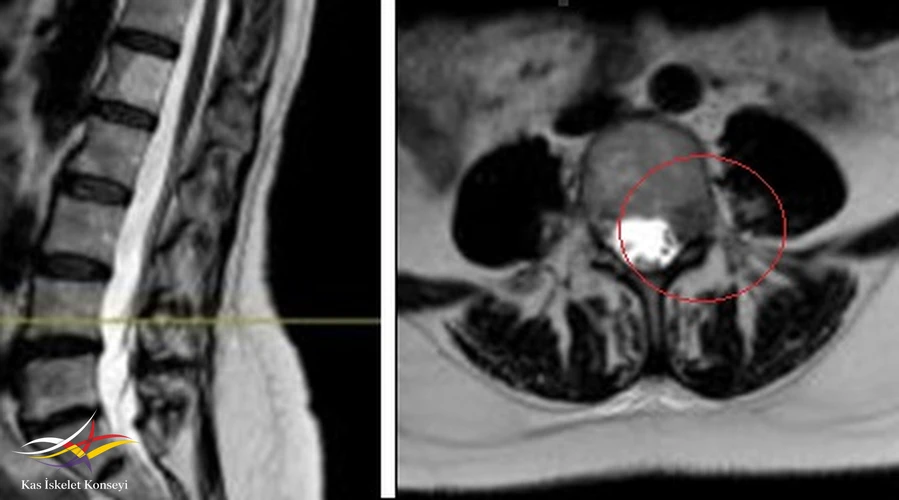

- Lomber MRG: Disklerde yükseklik kaybı veya anüler yırtık yok. L4-5 te solda forameni içinde, kök üzerinde şüpheli bir lezyon lezyon saptanması üzerine yapılan kontrastlı MRG'de lezyonda yoğun ve homojen kontrast tutulumu görüldü ve kitle lehine yorumlandı.

Resim 1. Lomber MRG'de L4-5 seviyesinde sol nöral foramende kitle imajı görülüyor.